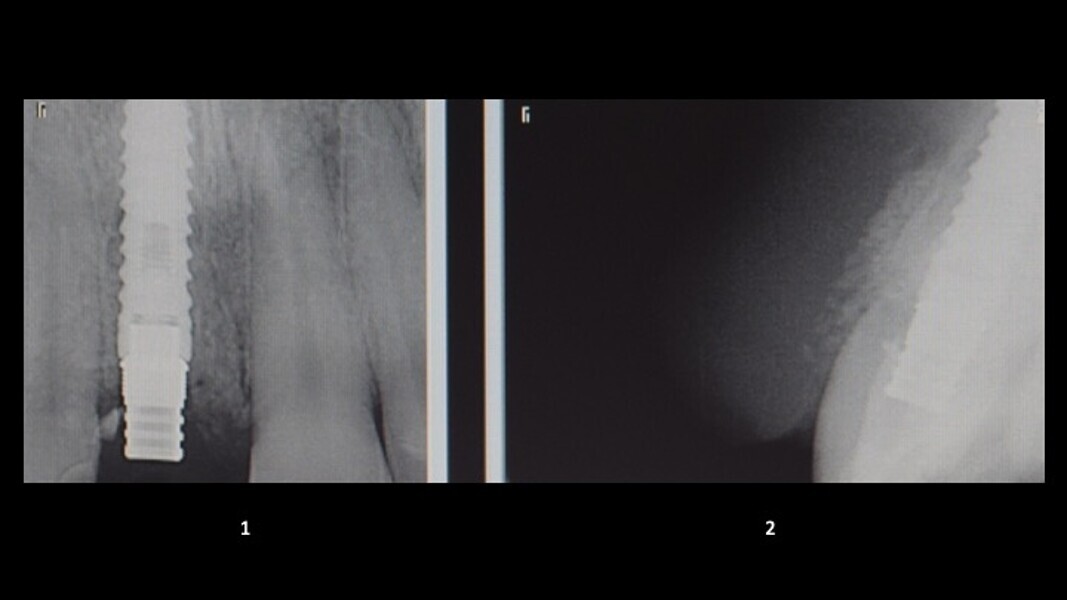

Figuras 2 y 3. Imágenes de tomografía CBCT donde se observa el grado de destrucción de la pared vestibular.